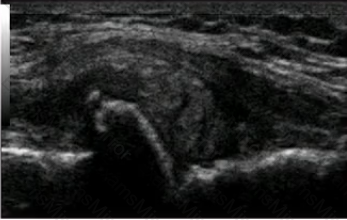

The image below shows the injection of the dorsal wrist region in a patient with rheumatoid arthritis. The needle is indicated by the arrows. Considering the ultrasound findings, which of the following is MOST appropriate in completing the injection?